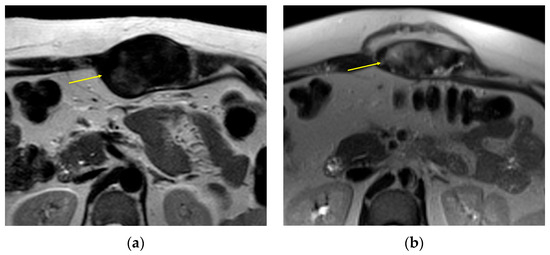

Figure 2.

Top row, a 23-year-old man with a left popliteal mass DT, pretreatment (a) and posttreatment (b) axial MRI T1 postcontrast with fat saturation images showing multifocal interval decrease in contrast enhancement (arrows), despite grossly stable size of tumor. Bottom row, a 58-year-old woman with a similar location DT, pretreatment (c) and posttreatment (d) axial fluid sensitive fat-suppressed MRI images showing interval loss of central T2 hyperintense signal (arrow). Both patients were classified by RECIST as stable disease due to a lack of size change.